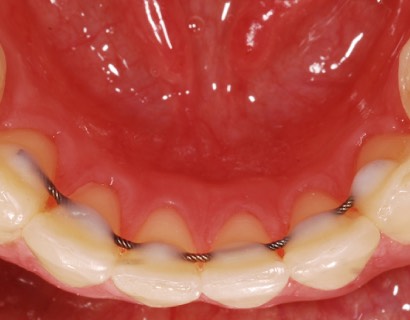

Несъемная ретенционная конструкция представляет собой тонкую, почти незаметную проволоку из специального сплава. Ее крепят на язычную (внутреннюю) сторону зубов. Проволока изготавливается из биологически инертного сплава, не вызывающего аллергических реакций.

Однако ни несъемный ретейнер, ни, тем более, съемный не мешают чистить зубы. Установку несъемного аппарата рекомендуется производить после гигиены. Между ретейнером и эмалью не остается бактериального налета, который мог бы вызвать кариес или воспаление. А потому его установка абсолютно безопасна для эмали.

Особых затруднений те, кто носят ретейнеры, не испытывают. При ношении несъемного аппарата зубы чистятся так же, как обычно. Однако тем, кто их носит, рекомендуется применять ирригатор. Он нужен, чтобы удалить частички пищи, которые могут задерживаться между зубов. Использовать зубную нить при ношении несъемного ретейнера может быть затруднительно. Несъемные аппараты нужно хранить в специальном кейсе, периодически промывать под водой, а также раз в сутки помещать в антисептический раствор.